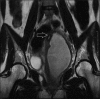

Figure 1b

Open arrow showing communication of collection with left uterine body